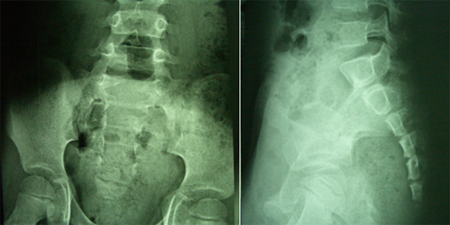

男性,4岁,腰臀后肿物切除术后4年,二便失禁4年。入院查体:臀部上方横形切口瘢痕,约5cm,肛门外口有残留粪便,肛门括约肌松弛,鞍区针刺痛觉减退,耻骨上叩诊浊音。B超:膀胱残余尿量约200ml。术前影像学图片示:先天性腰骶管脊柱裂,脊髓圆锥牵张低位,皮下脂肪疝入椎管内并和脊髓及神经根粘连,脊髓拴系形成。